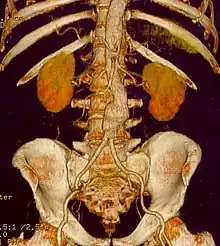

Open infrarenal aortic repair model, showing a surgical clamp above the aneurysm and below the renal arteries